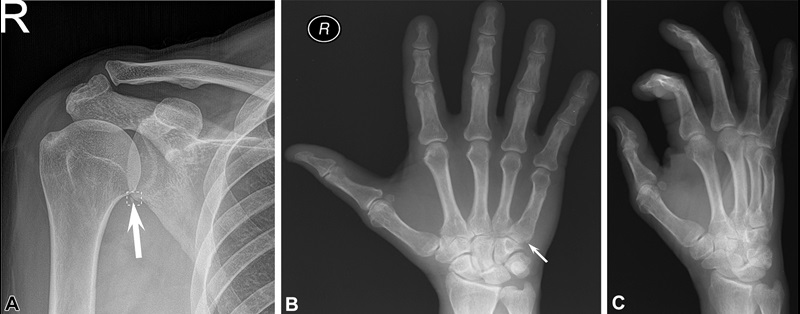

Stand-alone artificial intelligence (AI) performance examples: false-positive and false-negative radiographs. (A) Radiograph shows a small corticated ossific fragment adjacent to inferior glenoid margin (arrow), likely sequela of prior trauma (chronic fracture) or calcified detached inferior labrum rather than acute fracture. AI noted this as an acute fracture using the DOUBT-FRACT threshold. Fifteen readers read this as acute fracture without AI. Four readers thought the fracture was chronic without using AI, but reversed their reading with AI. Only two radiologists, one rheumatologist, and two family medicine physicians recognized the chronicity of the fracture with and without AI. (B) Radiograph shows a subtle nondisplaced fracture of the fifth metacarpal base (arrow), which was not detected by AI. All readers missed this fracture with and without AI. Only ground truth readers noted the fracture. This fracture was only appreciable on the anteroposterior view shown here and was not clearly visible on (C) the oblique view or the lateral view (not shown) of the right hand. There were two predefined thresholds for fracture detection: high-sensitivity threshold named DOUBT-FRACT, equal to 50% after transformation, and high-specificity threshold named FRACT, equal to 90% after transformation.

https://doi.org/10.1148/radiol.210937 © RSNA 2022